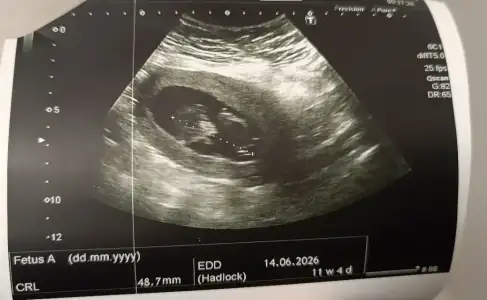

Arkasi dönük bilmem ki tahmin olur mu 11+4 teki görüntü buydu. (Şimdiye kadarki tek görüntü)